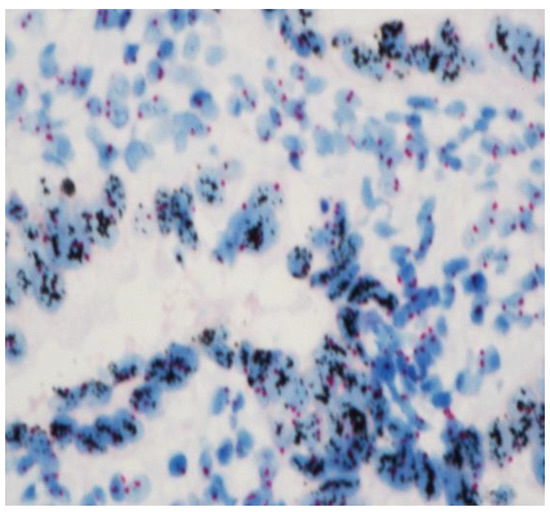

The slides were again reviewed by two experienced pathologists in order to classify the cases according to their immunohistochemical classification, as seen in (Table 1) and Figure 2.

To finalize our description, in the cases with an immunohistochemistry “++” or “+++”, to determine if a gene was amplified, CISH (Chromogenic In Situ Hybridization) was performed [17]. The VentanaBenchMark Ultra Plus IHC/ISH (Roche Diagnostics) was used. Cell conditioning 2 was used for the pretreatment and CISH protease 3 for enzyme digestion and finally incubation with HER2 (dinitrophenol-labeled) and chromosome 17 (digoxigenin-labeled). The HER2 probes were incubated with antidinitrophenol antibody and horseradish-peroxidase-conjugated antibody and then silver reactions. The CEP17 probes were incubated with anti-digoxigenin antibody and alkaline-phosphatase-conjugated antibody, and then a red CISH Naphtol reaction was induced. Ventana hematoxylin II and bluing reagent were used to counterstain slides [18]. At least twenty nuclei, each containing red (Chr 17) and black (HER2), were enumerated (Figure 3). The HER2 status is based on the ratio formed by dividing the sum of HER2 signals for all nuclei divided by the sum of chromosome 17 signals. The amplification status is defined if the HER2/Chr17 ratio ≥2.0.

Figure 3. HER 2-amplified endometrial carcinomas with clusters of HER2 signals in black clearly contrasting with the 2 red signals (Chr 17) at ×40.